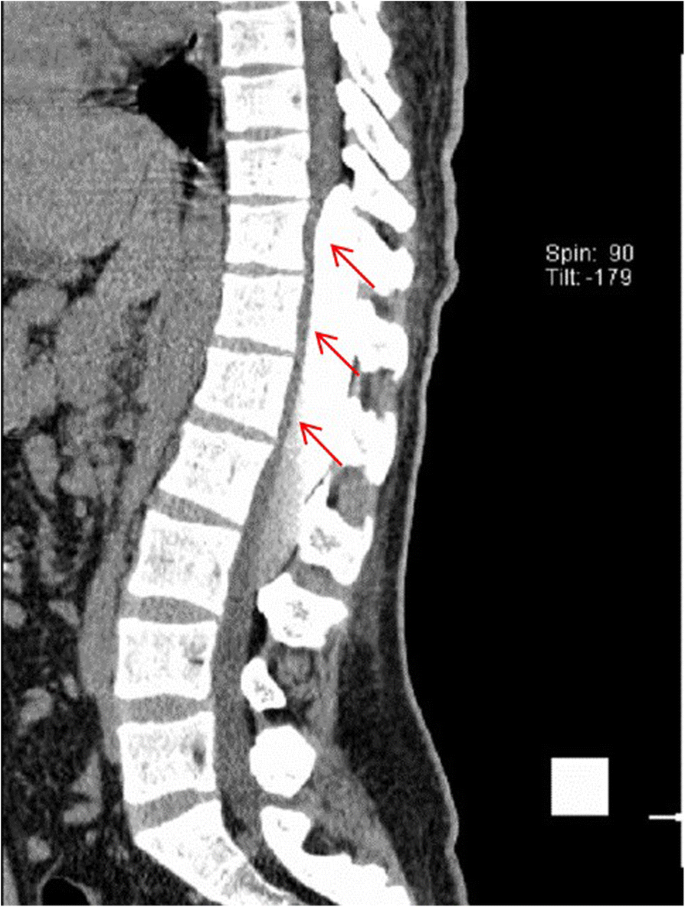

This is a 26-year-old man who experienced right lower limb weakness for 2 years and the weakness exacerbated in last half year. He visited the second affiliate hospital of the Zhejiang University School of Medicine. A physical examination indicated the result of the straight leg raising test was positive and also muscle atrophy. The muscle power of the right lower limb had decreased to grade 3. There was no sensory impairment. Magnetic resonance imaging revealed an intraspinal extradural tumor over T10 to L3 (Fig. 1). It appeared to be a spinal extradural arachnoid cyst (SEAC). To confirm whether the fistula existed between the subarachnoid space and arachnoid cyst, and to localize the position of the fistula, we performed a real-time technique. First, we injected contrast medium into the cyst under fluoroscopy. After 1 h the follow-up computed tomography (CT) was administered, and it revealed there was no contrast-infiltration into the subarachnoid space (Fig. 2). We then extracted about 20 mL of fluid from the cyst. The follow-up magnetic resonance imaging on the same day indicated the cyst did not become smaller (Fig. 3). A “one-way valve” fistula was suspected such that cerebral spinal fluid could pass into the cystic space from the subarachnoid space but could not flow in the opposite manner. Therefore we designed a procedure to localize the fistula. We penetrated two needles into the cyst and subarachnoid space separately in the L3/L4 level under digital subtraction angiography (Fig. 4). Pending the fluid drained through those two needles, we injected 10 mL of contrast medium slowly into the subarachnoid space and a little contrast medium infiltrated into the cystic space horizontally at the T12/L1 level. We then administered high resolution computed tomography (HRCT) immediately to confirm the position in the axial plane. The HRCT revealed a funnel-shaped enhancement between the lower edges of the T12 body and the left nerve root, and this is the accurate position of the fistula (Fig. 5).